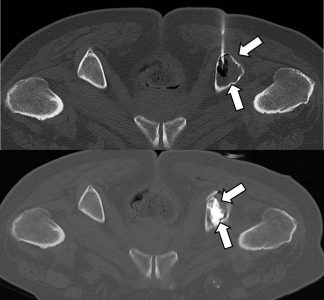

Η διαδερμική βιοψία είναι μια ελάχιστα επεμβατική μέθοδος λήψης υλικού από τον όγκο για κυτταρολογική και ιστολογική εξέταση από εστιακές αλλοιώσεις του ήπατος, του πνεύμονα, του μαστού, του νεφρού κλπ. Συνιστάται από τον κλινικό ιατρό ανάλογα με το είδος και το μέγεθος της βλάβης και πραγματοποιείται με ασφάλεια από επεμβατικό ακτινολόγο συνήθως με την καθοδήγηση αξονικού τομογράφου ή υπερήχων. Στη σύγχρονη ογκολογική θεραπεία, όπου γίνεται προσπάθεια καταπολέμησης του καρκίνου σε μοριακό επίπεδο, κρίνεται αναγκαία η ακριβής ιστολογική ταυτοποίηση του όγκου, ώστε να εφαρμοσθεί εξατομικευμένη θεραπεία για το βέλτιστο αποτέλεσμα.

Διαδερμικά κατευθυνόμενη βιοψία παρα-αορτικού λεμφαδένα σε λέμφωμα Hodgkin

Ακτινολογία

Διαδερμικά κατευθυνόμενη παρασπονδυλική βιοψία μικροκυτταρικού καρκινώματος πνεύμονα

Διαδερμικά κατευθυνόμενη θεραπεία καρκινικού πόνου με οστεκατάλυση και οστεοπλαστική σε ασθενή με οστικές μεταστάσεις λεκάνης από καρκίνο θυρεοειδούς